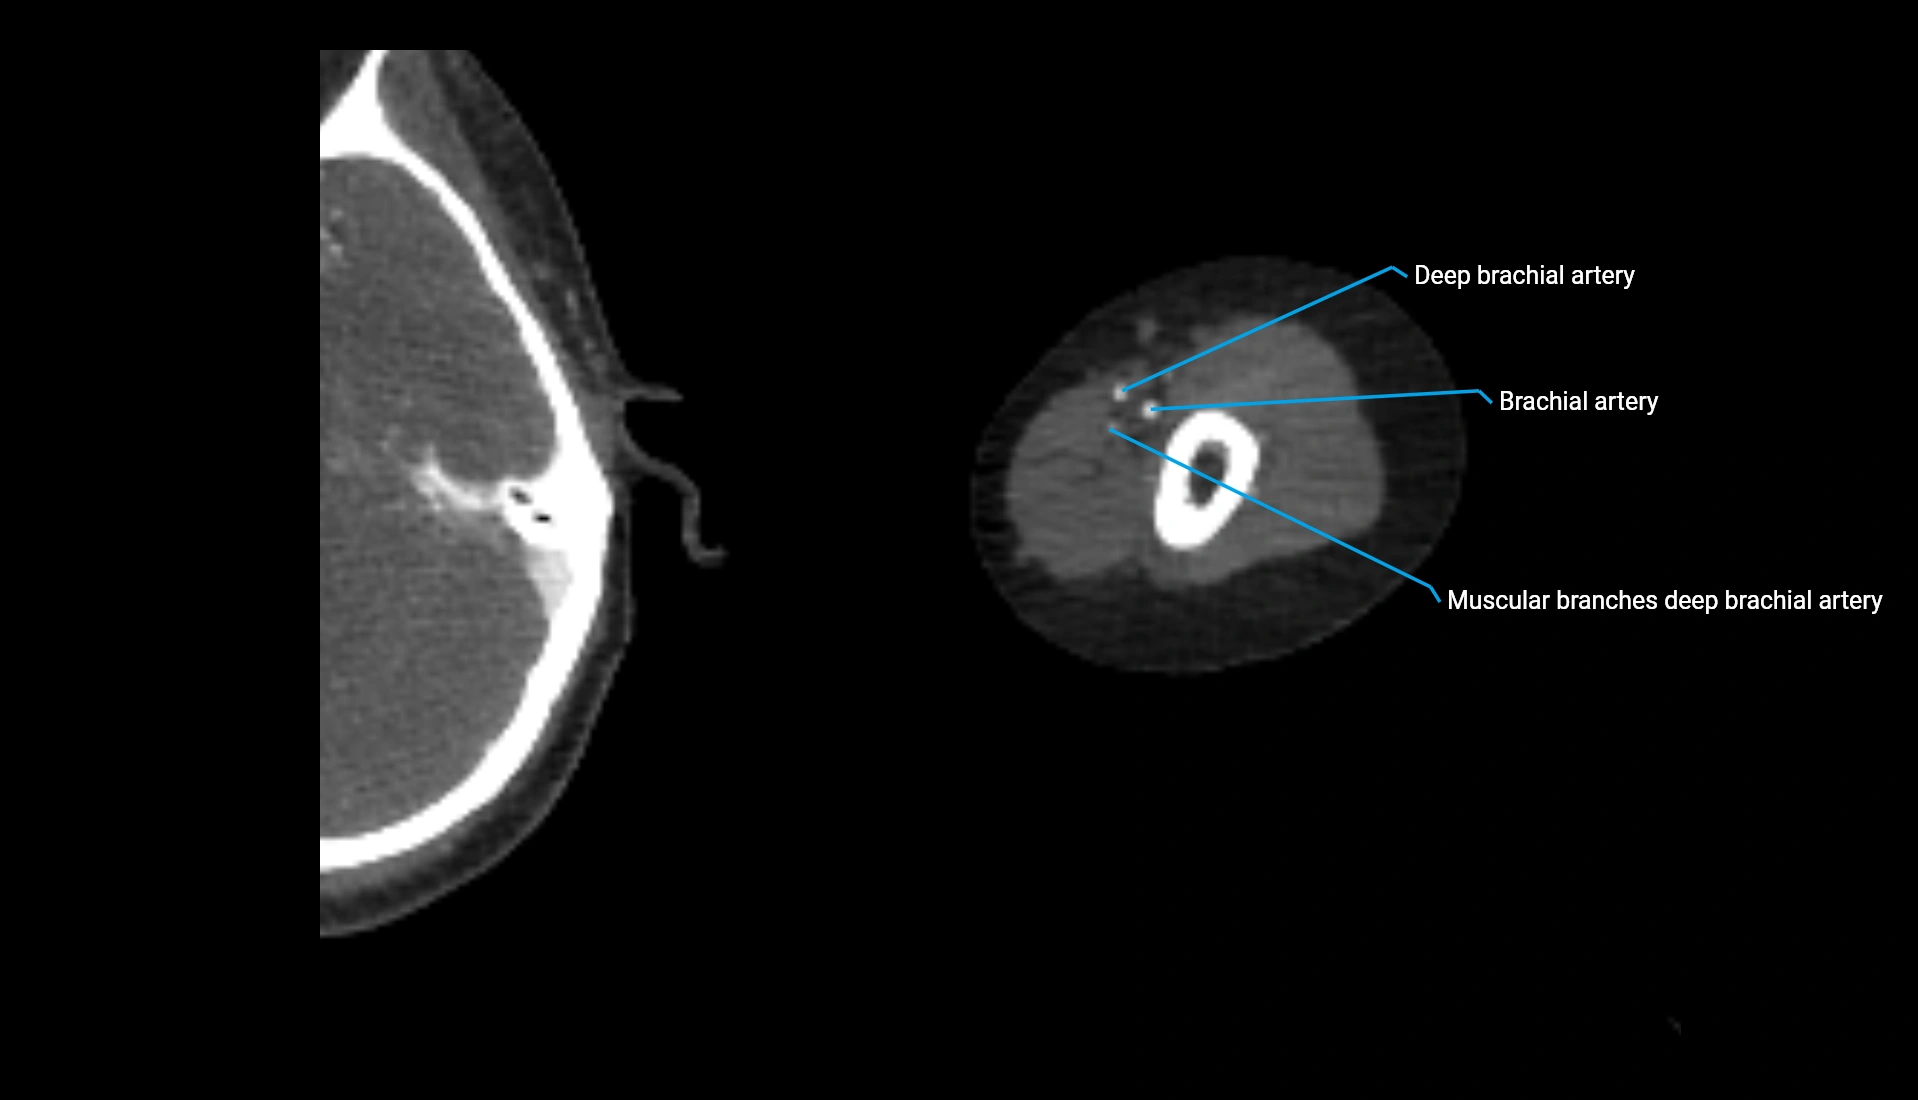

CT Appearance

Non-Contrast CT:

• Cortex: High-density, sharply defined

• Subchondral bone: Dense cancellous matrix

• Articular surface: Smooth concave contour articulating with the capitellum

• Excellent for evaluating bone integrity, alignment, and subtle fractures